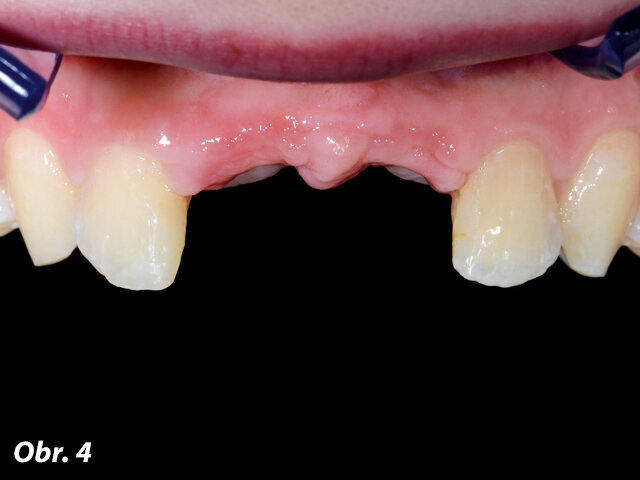

Při první návštěvě pacientky bylo zjištěno, že laterální řezáky měly rozsáhlé kompozitní rekonstrukce, a to na vestibulárních ploškách a z důvodu předcházející rehabilitace adhezivním můstkem také na palatinálních ploškách (obr. 4).

Obr. 4: Situace při první návštěvě mladé pacientky v soukromé zubní ordinaci na LMU v Mnichově